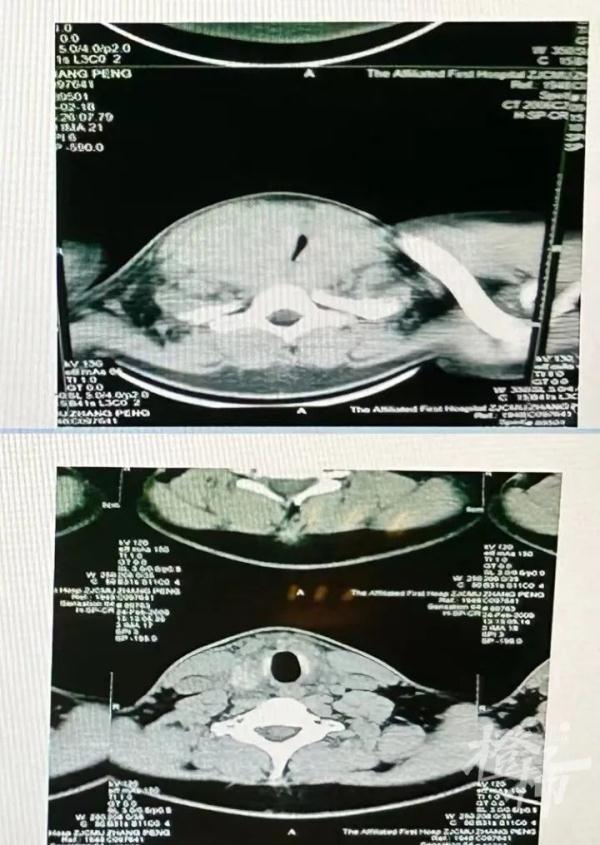

20歲的小雨也有類似的經歷,他比小玲的情況更嚴重,他來醫院時吐氣都很困難,睡覺時出現了嚴重的打呼聲,甚至影響到了在隔壁睡覺的父母。通過甲狀腺B超檢查,小雨的氣道被甲狀腺腫瘤嚴重壓迫?!霸就〞车臍獾辣粔浩鹊街皇R坏罉O窄的縫隙,所以他才會出現吐氣困難、打呼嚴重的情況?!备到淌谡f。手術后,小雨終于恢復正常,能夠順暢吐氣了。

小雨手術前后的氣道對比圖。(醫院供圖)